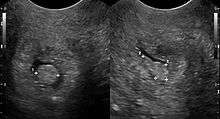

Cervical polyps are finger-like growths, generally less than 1 cm in diameter.[3][5] They are generally bright red in colour, with a spongy texture.[4] They may be attached to the cervix by a stalk (pedunculated) and occasionally prolapse into the vagina where they can be mistaken for endometrial polyps or submucosal fibroids.[5]